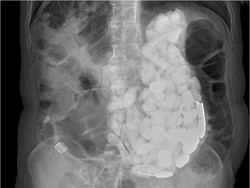

Para dokter mengeluarkan batu, tutup botol, hingga koin dari perut seorang pria yang memiliki kebiasaan aneh. Ia selalu makan benda aneh ketika merasa cemas.